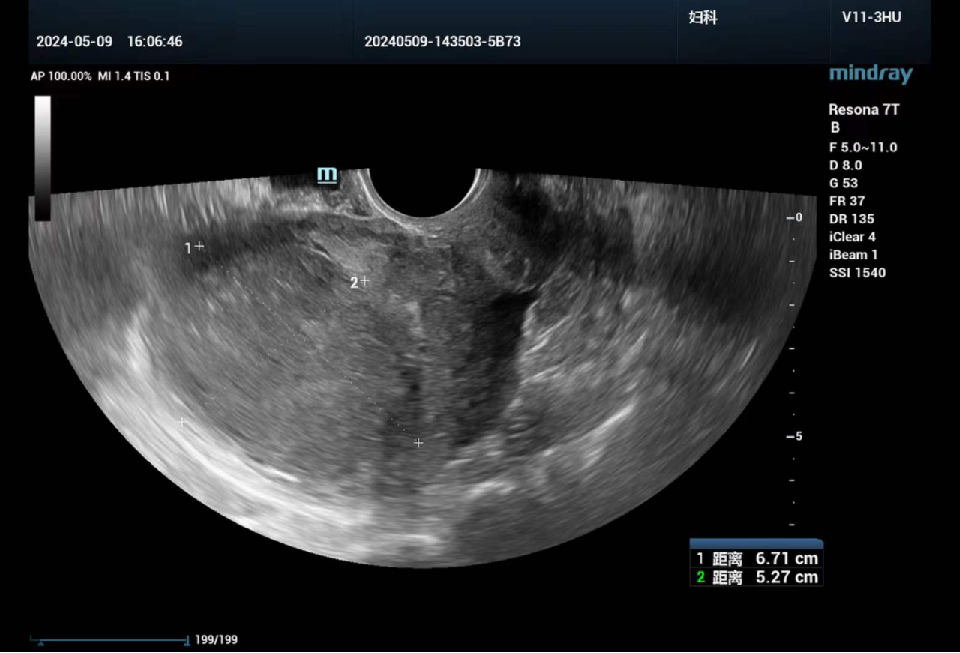

女性,51岁

发现子宫肌瘤2月余。现病史:平素月经规则,7/30天,量中,末次月经2024-4-17,近2年月经周期缩短为23天,月经量较前增多;

妇科超声提示子宫内膜厚0.8cm,子宫前壁探及两枚低回声团块,较大约6.6cm×5.6cm,与内膜相贴,内部回声不均。后突然出现阴道大量出血,急诊就诊霍邱县人民医院血红蛋白89g/L,急诊行分段诊刮术,术后病理:(宫颈管)黏膜慢性炎,(子宫内膜)增生期内膜腺体,部分腺体单纯性增生过长,间质较致密

辅助检查

经腹超声和经阴道超声检查